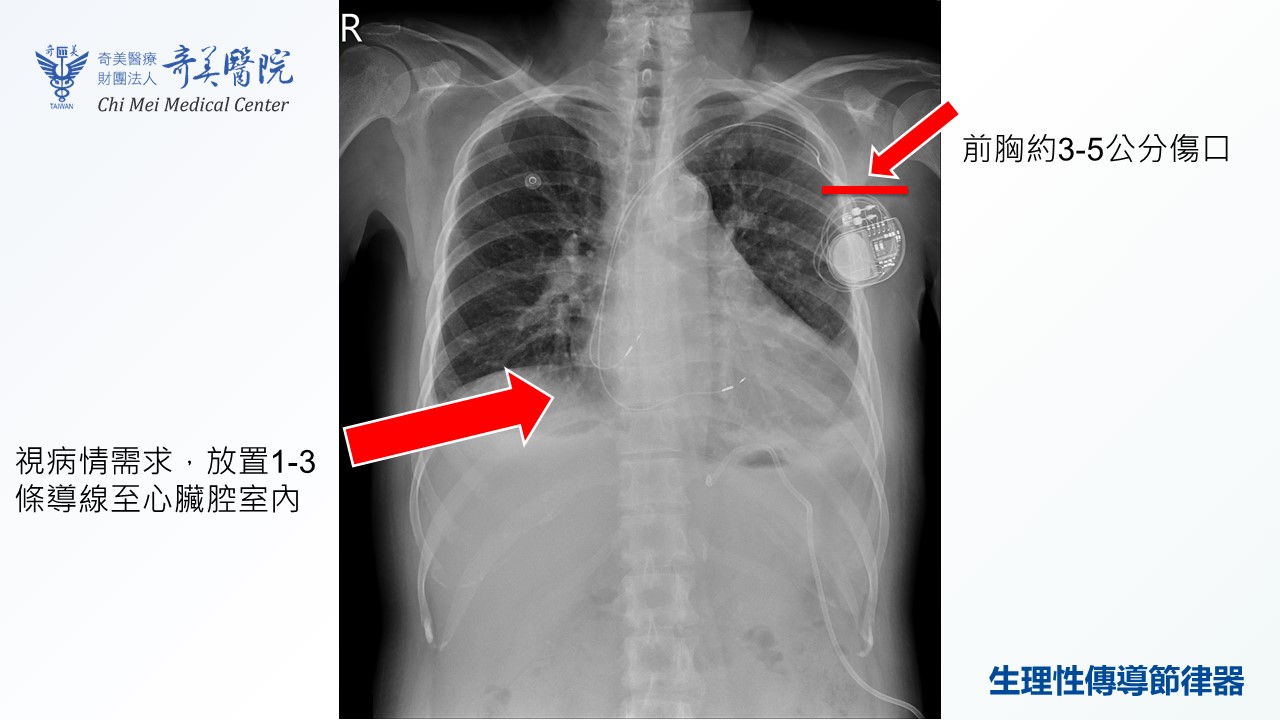

黃沛頡指出,體內心臟節律器置放至今已有接近70年之歷史,安全性與成效皆相當成熟。近十多年來,因科學及技術的進步,醫學界更研發出了「生理性傳導」技術。不同於傳統節律器,有時會因心室收縮不同步,進而引發「節律器引起之心衰竭」;生理性傳導技術透過「希氏束」、「左束支」及「巴赫曼氏束」進行精準起搏,能夠提供病人更加天然、自然的節律。多項臨床研究證實,這種方式能減緩心臟功能下降、減少心房顫動復發,對於特定病人甚至能改善心臟衰竭症狀。

黃沛頡進一步說明,根據統計,臺灣約二十年前每年有2,000至4,000名病人接受心臟節律器置放。近年來,每年需要心臟節律器的病人數量逐漸增加到約7,500人。針對日益增加的節律器需求,奇美醫院近年在「心室型生理性傳導」技術已累積成熟經驗。2025年更進一步引進心房型「巴赫曼氏束」生理性傳導技術,提供全方位的生理性節律。雖然生理性傳導技術因需精準定位,手術時間會比傳統手術多出0.5至1.5小時,且須視病人解剖構造決定能否施作,但在適合的條件下,可大幅提升治療品質。

生理性傳導技術因需精準定位,手術時間會比傳統手術多出0.5至1.5小時,且須視病人解剖構造決定能否施作,但在適合的條件下,可大幅提升治療品質